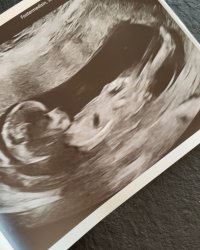

GuttNoen som vil gjette på disseSynes det er så vanskelig og vite siden begge bildene er så forskjellig, så vet ikke om det ene bildet er nuben som peker sykt opp, eller om det er den lille andre greia under. Chat gtp sa jente på begge, men vet jo at den ikke er til å stole på, så jeg tror kanskje noe annet

Det kommer en liten jente til oss, så du hadde rett her! Det blir skikkelig stas etter 3 gutter!Ja, lov og si at det kanskje blir litt ekstra stas med jente da. Jeg synes den peker rett frem, så holder en knapp på jente. Du må oppdatere meg. Jeg har en gutt fra før, og håper jo litt på motsatt kjønn. Men legen trodde det var gutt hos oss igjen. Og det blir også veldig koselig med brødre![]()